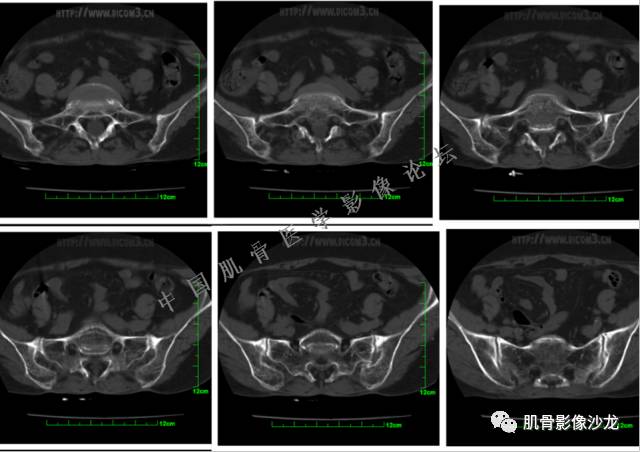

患者于2月前无明显诱因下出现腰骶部疼痛,夜间为重,逐渐加重伴左下肢麻木、疼痛,并有行走活动受限,在我院就诊,摄腰椎及骶髂部CT提示:腰椎骨质退变,腰3-4、4-5椎间盘膨出,骶髂关节炎。自用非甾体抗炎药无好转,再次来院就诊,门诊拟“骶髂关节炎”收住我科。病程无间歇性跛行,大小便正常。

专科检查:神清,脊柱无侧弯后凸畸形,椎体各节段无压、叩痛,双侧棘突旁无压痛,双侧骶髂关节压痛明显,左下肢放射痛,浅感觉较健侧减退,腰椎前屈后伸活动受限,膝、跟腱反射正常。

辅助检查:腰椎及骶髂部CT提示:腰椎骨质退变,腰3-4、4-5椎间盘膨出,骶髂关节炎。

雪舞 :第二例,位于骶骨,有骨质破坏并有软组织肿块,软组织肿块边界清

雪舞: 第二例我们能够看到破坏与软组织肿块不成比例,软组织肿块大,破坏小

雪舞 :第二例挺难的,骨质破坏是溶骨性的,局部皮质中断,软组织肿块外缘光滑